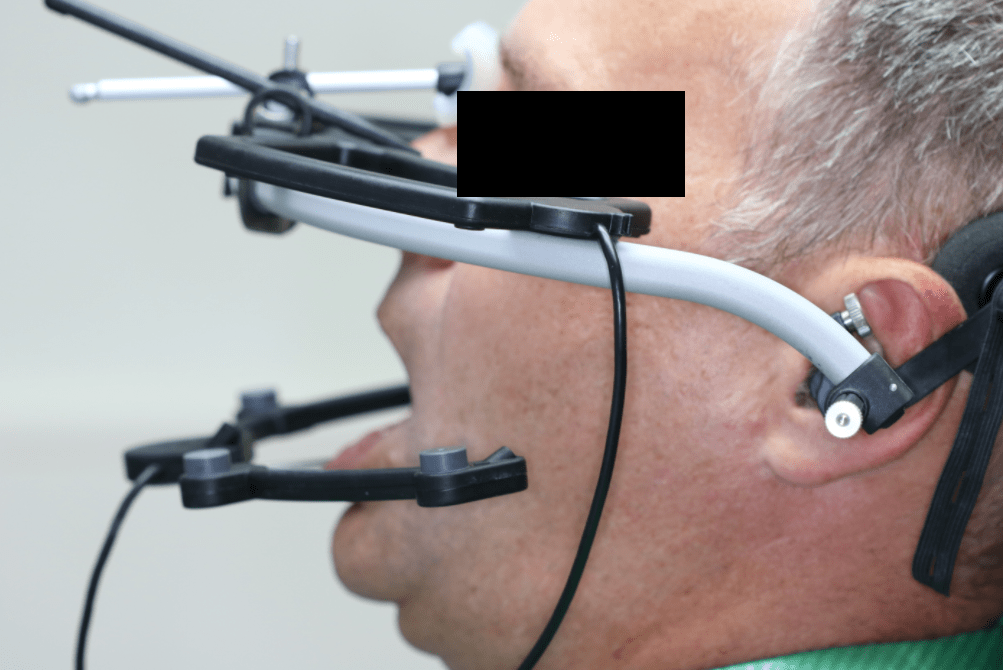

Szükség lehet speciális gyógytornára, egyénre szabott éjszakai sín hordására, akár megfelelő fogszabályozó készülék, illetve fogpótlás elkészítésére is. Ilyen esetekben speciális bemérésre van szükség, amihez úgynevezett nyílhegyrajzoló készüléket, arcívet, pozíciós harapásokat használunk, és segítségül hívhatjuk a legmodernebb, erre a célra létrehozott készüléket: az ARCUSdigmát.

Az állkapocs helyzetének, mozgásának megállapítására, esetleges hibáinak felderítésére az ARCUSdigma rendszer szolgál. A KaVo ARCUSdigma egy elektronikus regisztrációs rendszer, amely 3 dimenziós, ultrahangos méréseken alapul, a páciens egyéni alsóállkapocs-mozgásait méri a koponyához viszonyítva, minden olyan beállítási értéket kiszámít a fogtechnikusok számára, amelyek az artikulátor programozásához és az egyedi, funkcionális fogpótlások készítéséhez szükségesek.

Majd ezt követően arcívvel meghatároztam a felső állcsont koponyához való elhelyezkedését, intraorális rajzolóeszközzel a felső és az alsó állcsont egymáshoz való viszonyát, majd az Arcus Digma készülékkel az individuális mozgáspályákat. Ez mind szükséges ahhoz, hogy egyedi, az egyén számára legkényelmesebb fogpótlás elkészülhessen, melytől jelen esetben páciensünk panaszainak rendeződését vártam.